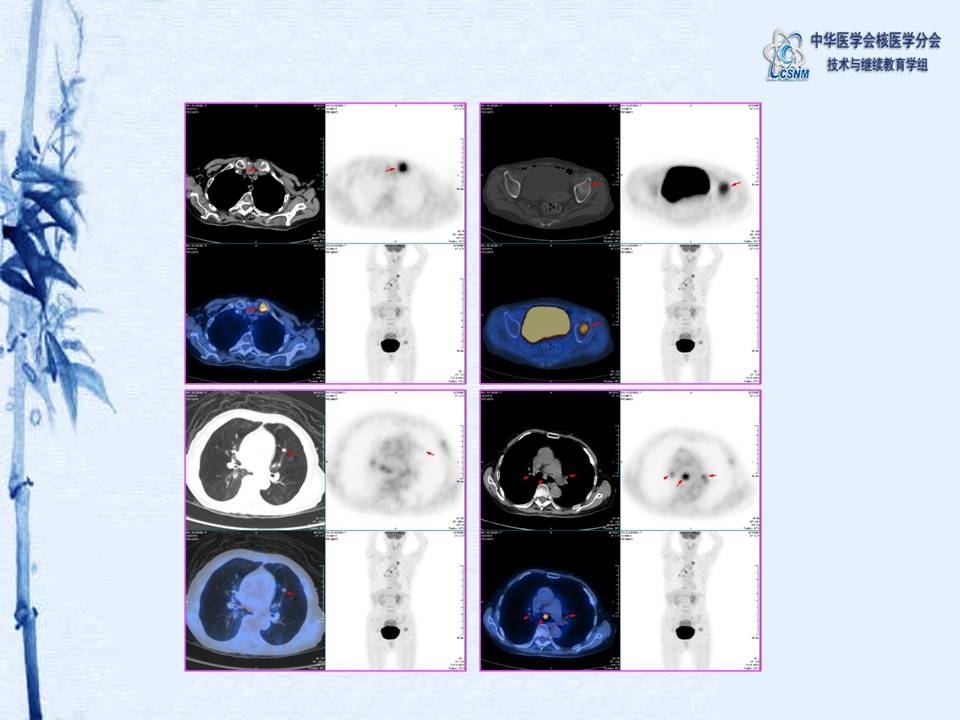

病例20:131碘全身扫描辅助诊断甲状腺癌多发骨转移一例-【CSNM继教学组】黄斌豪

【CSNM继教学组】黄斌豪 131碘全身扫描辅助诊断甲状腺癌多发骨转移一例).pdf